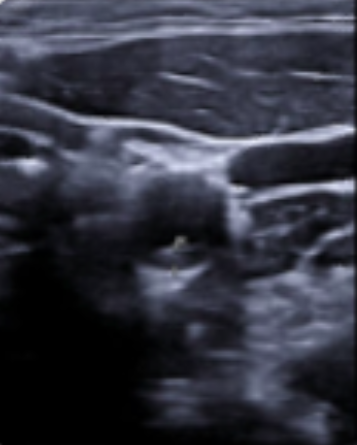

Los estudios de morbimortalidad reflejan que la enfermedad cardiovascular ocurre en más del 50% en varones y un 80% en mujeres catalogados de RCV bajo o moderado. En estudios sobre IAM el 50% de ellos presentaban uno o ningún FRCV. Así, podemos decir que existe un debate abierto sobre si las guías actuales infraestiman la arterioesclerosis ya existente, por lo que nos planteamos esta experiencia con la exploración ecográfica. Para ello realizamos una rotación en una unidad de RCV hospitalaria, con un protocolo específico para luego aplicarlo en el Centro de Salud. La valoración es similar a la utilizada en el Estudio PESA, donde se evalúa la existencia de placas de ateroma a nivel femoral, carotídeo, además de despistaje de aneurisma de aorta abdominal.

La ecografía es útil para valorar la arterioesclerosis mediante la detección de placa de ateroma en arterias carótidas y/o arterias femorales, indicando lesión de órgano diana (LOD) y llevándonos a facilitar la decisión de intensificar el tratamiento y así poder modificar la progresión de la enfermedad.